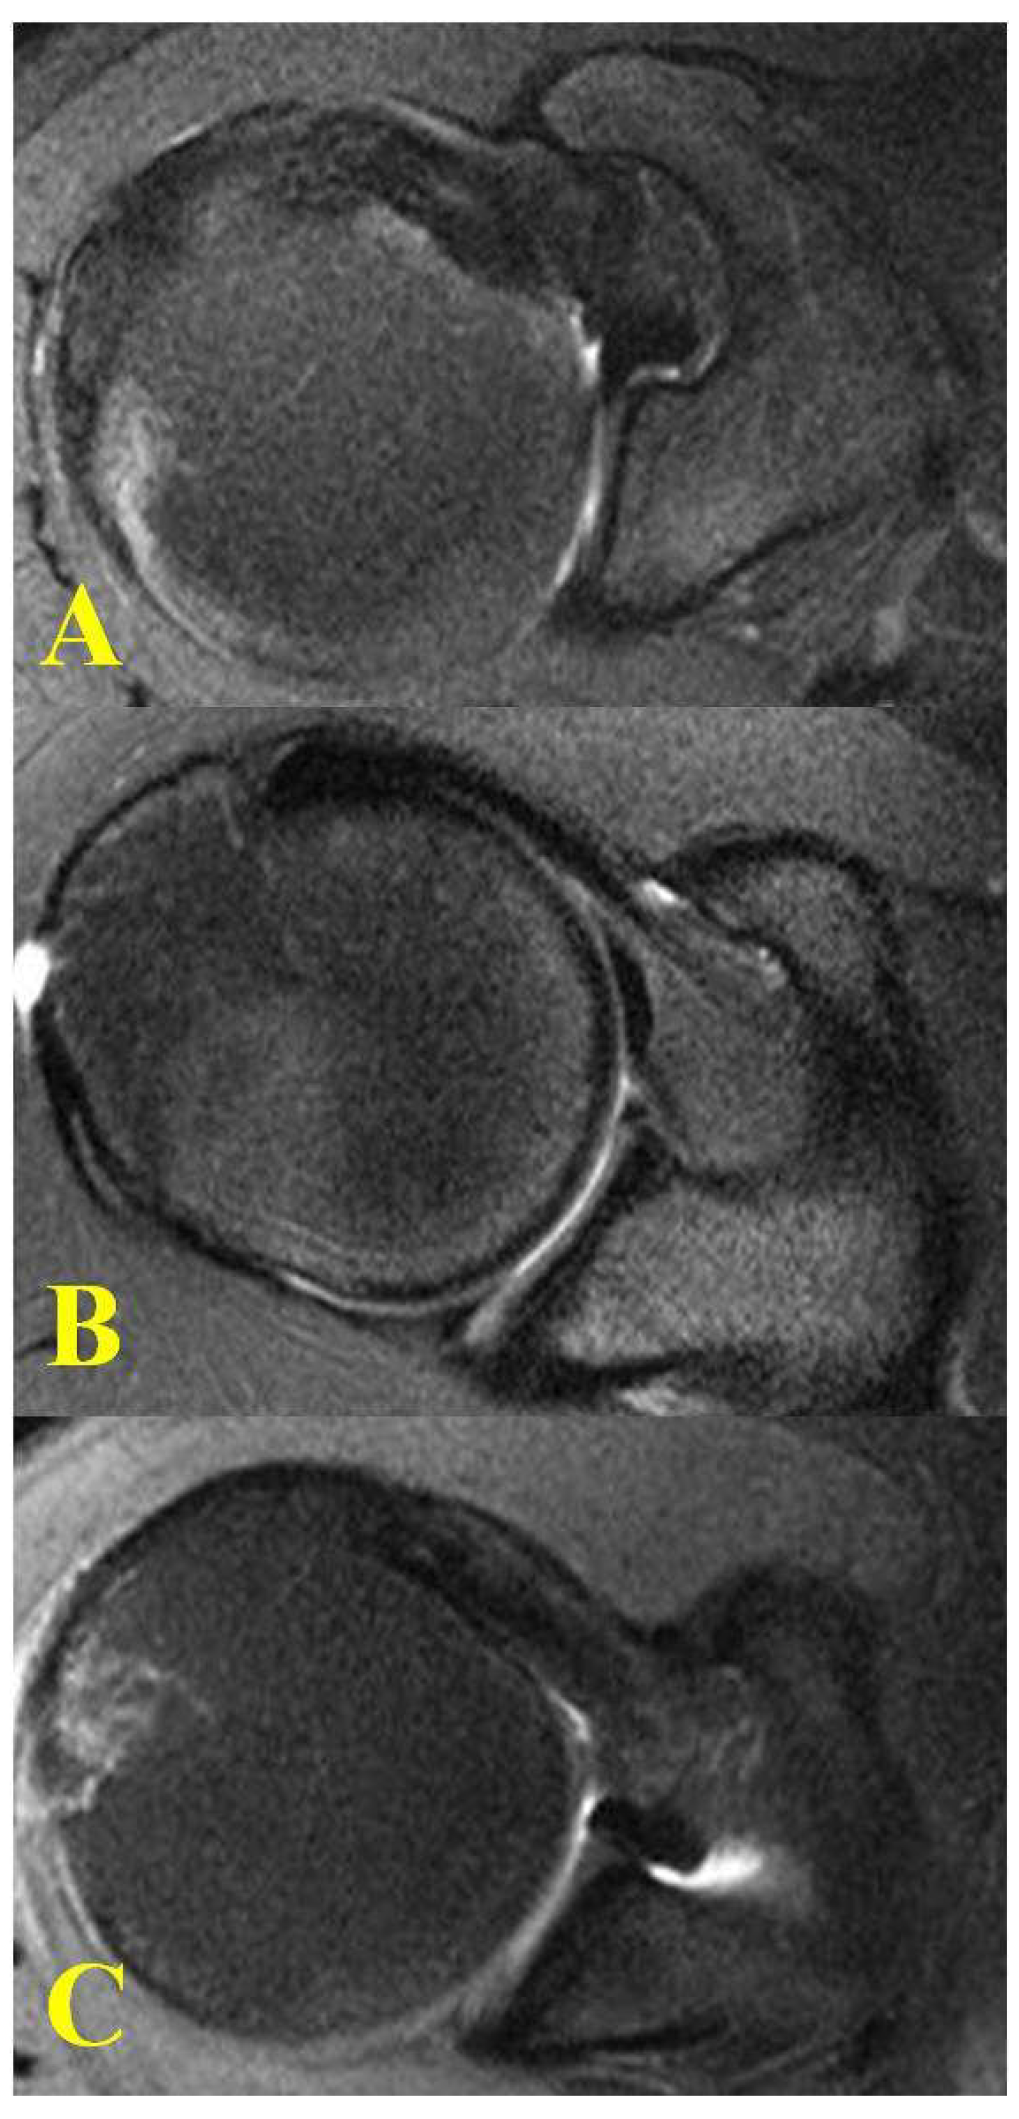

| Coracoid Morphology | |||

| Flat | 5 | 9 | 1 |

| Curved | 34 | 42 | 46 * |

| Hooked | 24 | 21 | 11 |